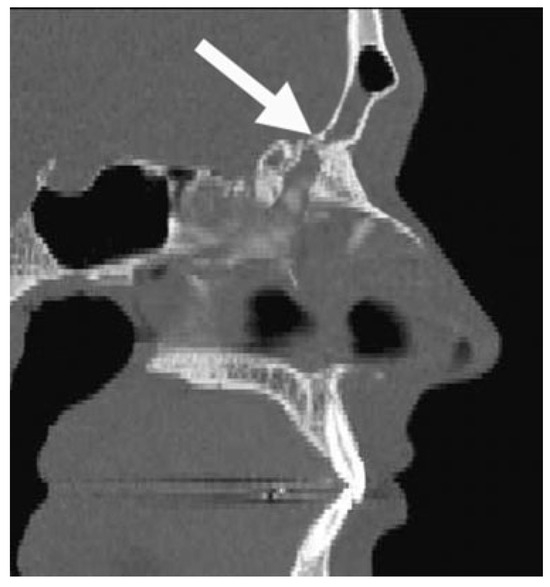

A thin-cut (1.0 to 1.5 mm) axial, coronal, and sagittal computed tomography (CT) scan is the radiological gold standard for diagnosis of frontal sinus fractures. Axial images provide the best information about the anterior and posterior tables (Figure 2); coronal images are used to assess the sinus floor and orbital roof (Figure 3). Sagittal reconstructions can be useful in assessing the patency of the frontal recess (Figure 4), and three-dimensional recon- structions may help to visualize the external contour deformity seen less clearly with two-dimensional cuts alone (Figure 5).

Figure 4.

Sagittal computed tomography scan demonstrat- ing a frontal sinus fracture. The arrow demonstrates narrow- ing and obstruction of the frontal sinus outflow tract.